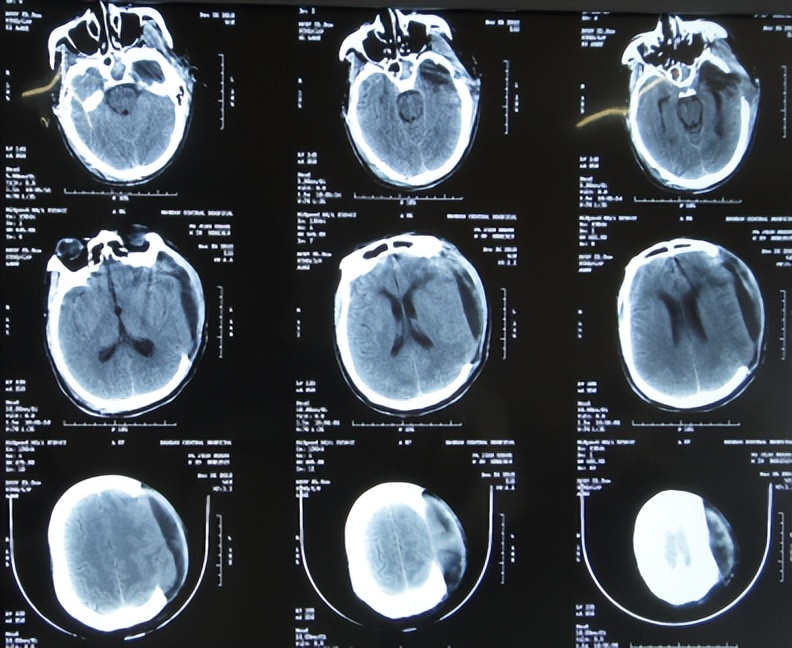

患者于2012年12月7日,骑电动车意外摔伤致脑外伤昏迷,急送往当地的河北省邯郸市的某三甲医院,查头颅CT示脑挫裂伤,有出血( 图-1 ),急诊给予了左额颞顶及右枕开颅颅内血肿清除并去骨瓣减压术,留置脑室外引流。患者既往病史:19岁时曾患肺结核已治好。

图-1: 2012年12月7日头颅CT

术后次日查头颅CT示开颅去骨瓣减压术后状态,有水肿( 图-2 )。

图-2: 2012年12月8日头颅CT

开颅术后5天即2012年12月12日,查头颅CT示仍有水肿,但拔除了脑室外引流管( 图-3 )。

图-3: 2012年12月12日头颅CT

开颅术后7天即2012年12月14日,查头颅CT示水肿有加重( 图-4 )。

图-4: 2012年12月14日头颅CT